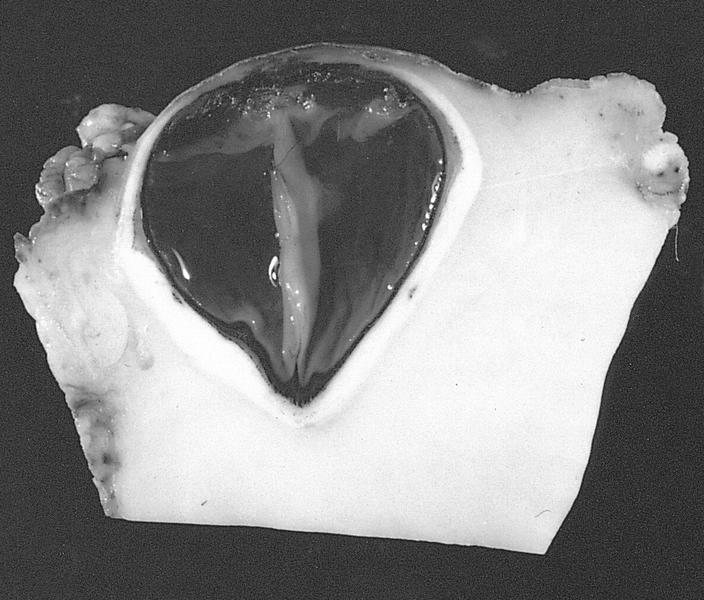

Gross description

Gross images

AFIP images

Gross description

- Indurated orbital mass, often surrounding optic nerve and enveloping extraocular muscles

Gross images

AFIP images